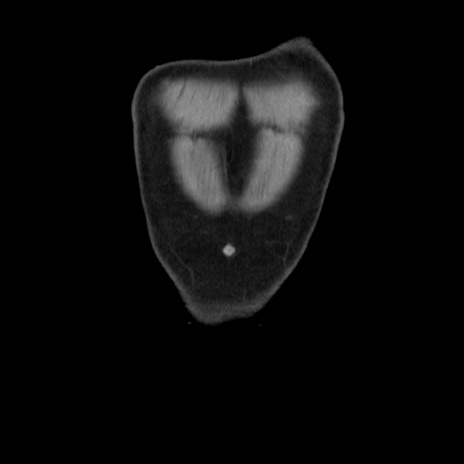

横断像